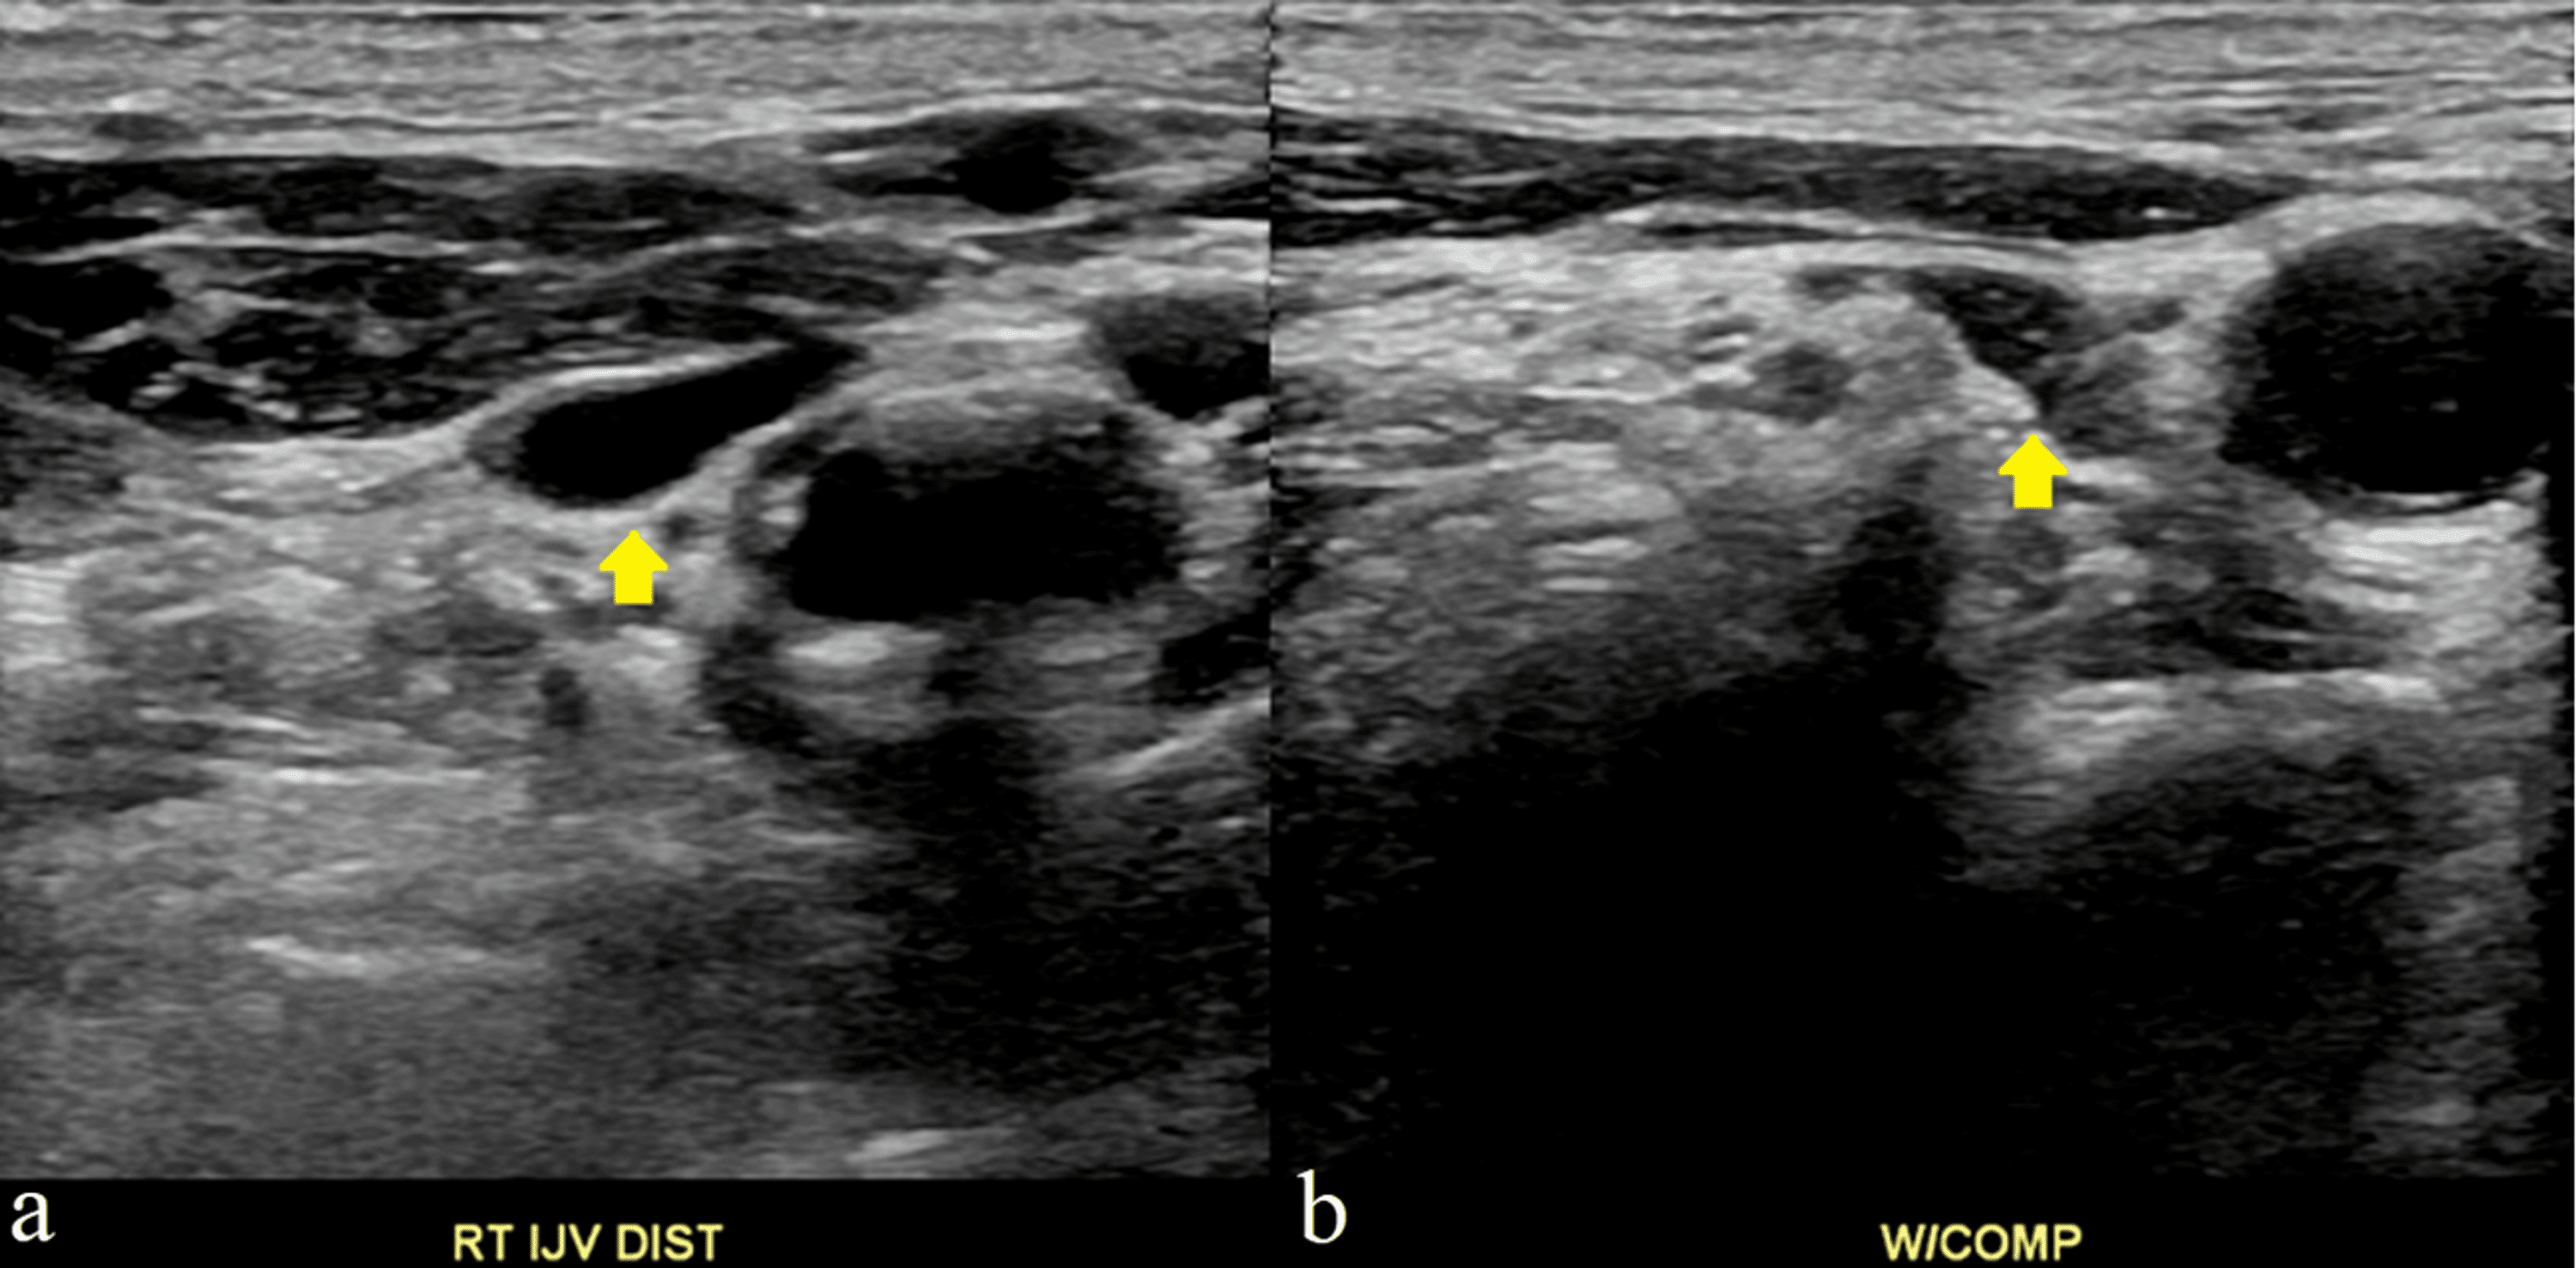

Internal jugular vein (IJV) imaging by B‐mode ultrasonography. Right Protruding Jugular Vein It's a key symptom of heart failure and other heart and. If you ever see someone with a bulging neck vein, you’re looking at the external jugular vein. evaluation of jugular venous pressure (jvp) involves observing the patient's jugular vein in the patient's neck in varying degrees of positions and. the jugular venous exam is an important aspect. Protruding Jugular Vein.